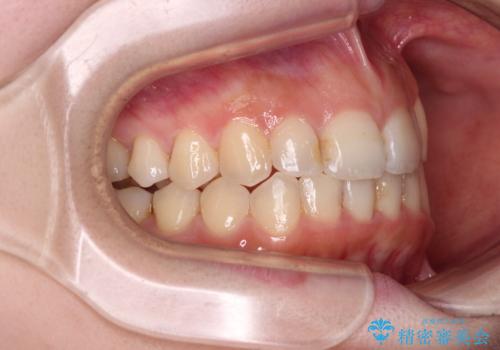

顕著な八重歯をインビザラインで治せるところまで改善

- 顕著な八重歯など、上下前歯のデコボコとスペースを気にして来院された患者様です。

八重歯改善には第一小臼歯の抜歯が必要であり、移動量が多いことから補助装置により八重歯を引き込むこととしました。

インビザラインでの治療をご希望であったので、インビザラインにて行うこととしましたが、右側前歯の改善にはワイヤー矯正が必要となる可能性があることをお伝えした上で治療を開始しました。

補助装置だけでなく、部分的にワイヤー矯正も使用しましたが、上下のスペースは改善しきれず、側切歯(前から2番目の歯)や顕著な八重歯は、インビザラインで治療するには限界があることがよく分かりました。

より良い仕上がりを希望される場合には、ワイヤー装置による矯正治療がお勧めとなります。